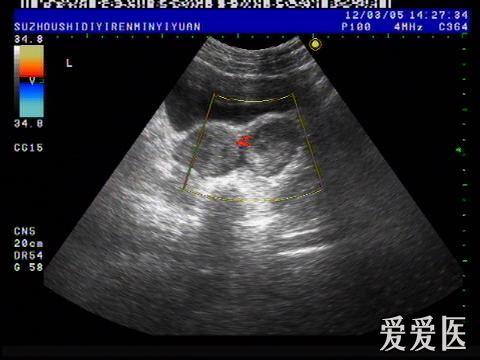

卵巢黄体血肿?

图片尺寸480x360